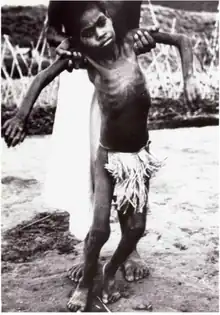

| A Fore child with advanced kuru. He is unable to walk or sit upright without assistance and is severely malnourished. | |

In the terminal stage, the infected individual's existing symptoms, like ataxia, progress to the point where it is no longer possible to sit up without support. New symptoms also emerge: the individual develops dysphagia, which can lead to severe malnutrition, and may also become incontinent, lose the ability or will to speak, and become unresponsive to their surroundings despite maintaining consciousness.[14] Towards the end of the terminal stage, patients often develop chronic decubitus ulcerated wounds that can be easily infected. An infected person usually dies within three months to two years after the first terminal stage symptoms, often because of aspiration pneumonia[15] or other secondary infections.[16]